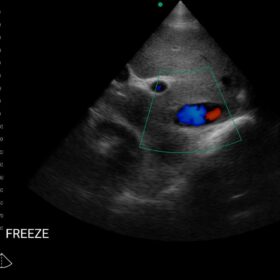

Cardio 2D, Color and PW doppler